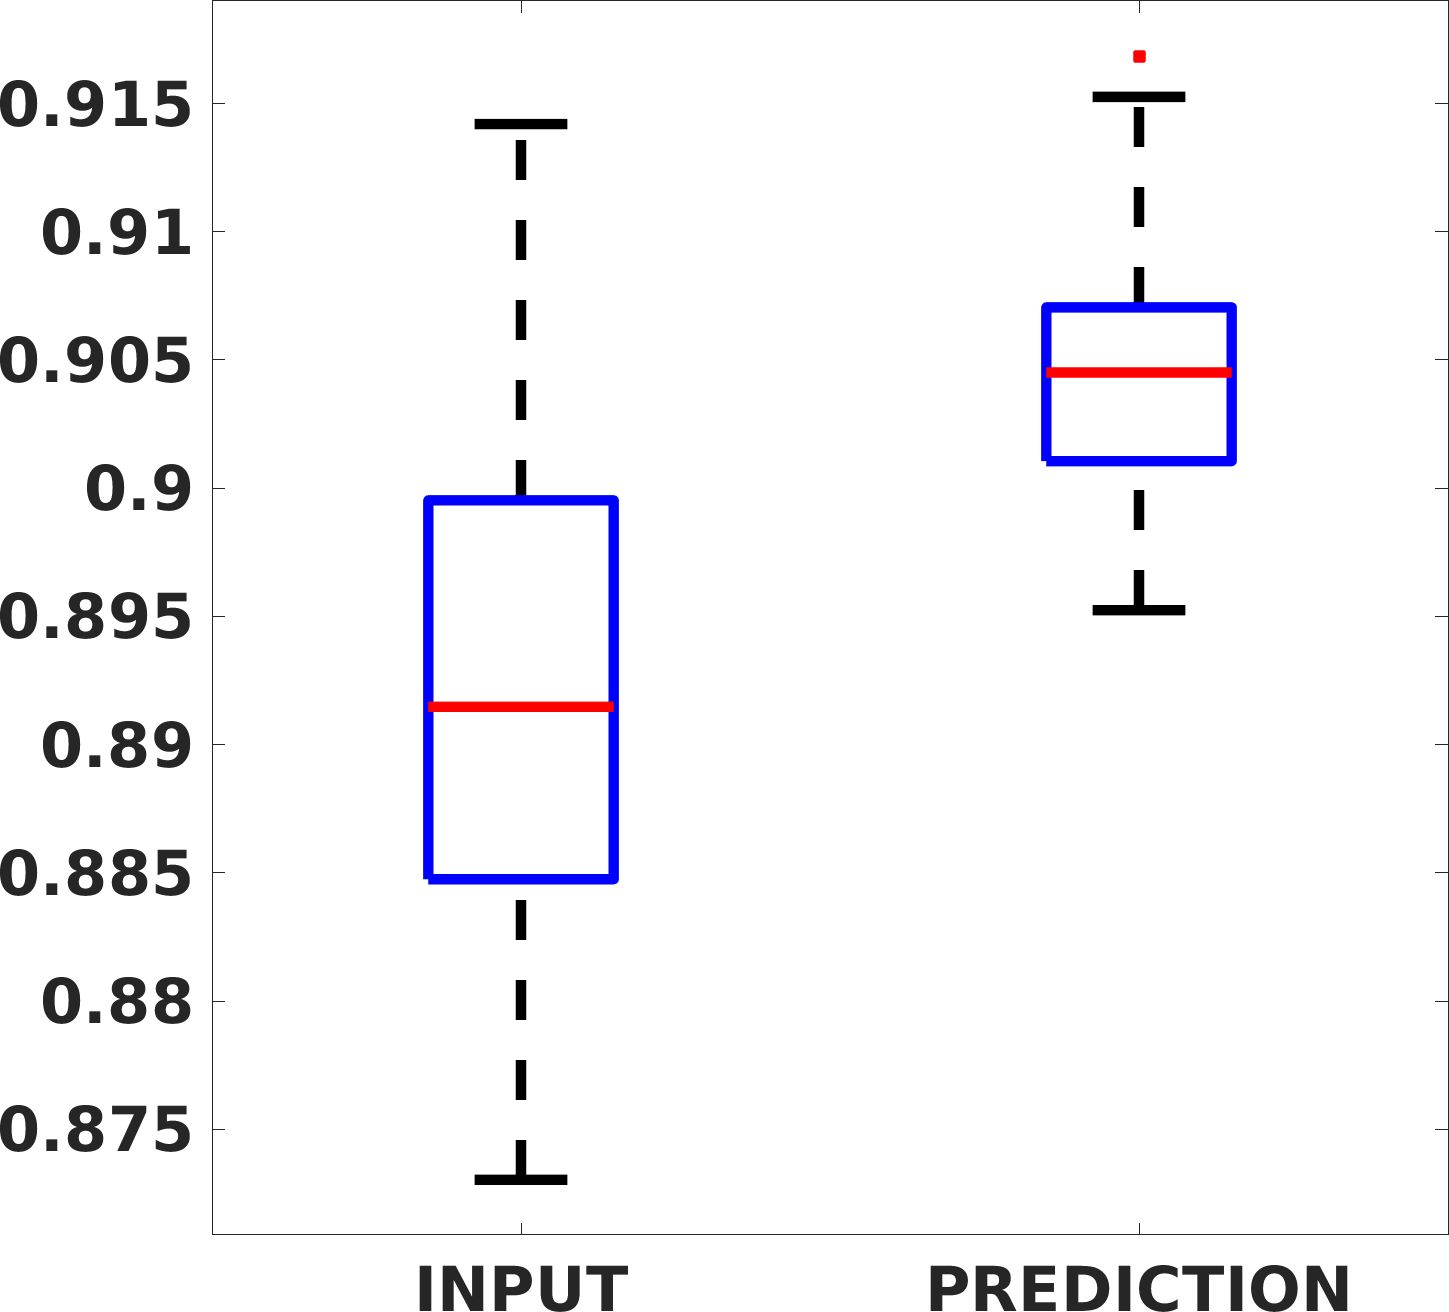

Fig. 8 shows the box plot of the SSIM (a-b-c, left) and MAE (a-b-c, right) quantitative metrics, as performed for PSNR metric. Also, these metrics show that our method improves the results of Cubic convolution both in terms of average value and variability. For example, the SSIM median value improves of on obstetric 4X images and the MAE median value improves of on cardiac 2X images.

Fig. 17 (right) shows the histogram of the absolute value of the error with respect to the target, of the prediction and Cubic convolution respectively. This result shows that our framework increase of and (2X and 4X, respectively) the number of pixels where the prediction error is lower than 5, which is very similar to the target when visually analysing the images, and improved with respect to the learning framework applied to raw images. According to Fig. 18, our method improves the accuracy of Cubic convolution. For example, the SSIM increases of on cardiac 2X and the MAE increases of on abdominal 4X.